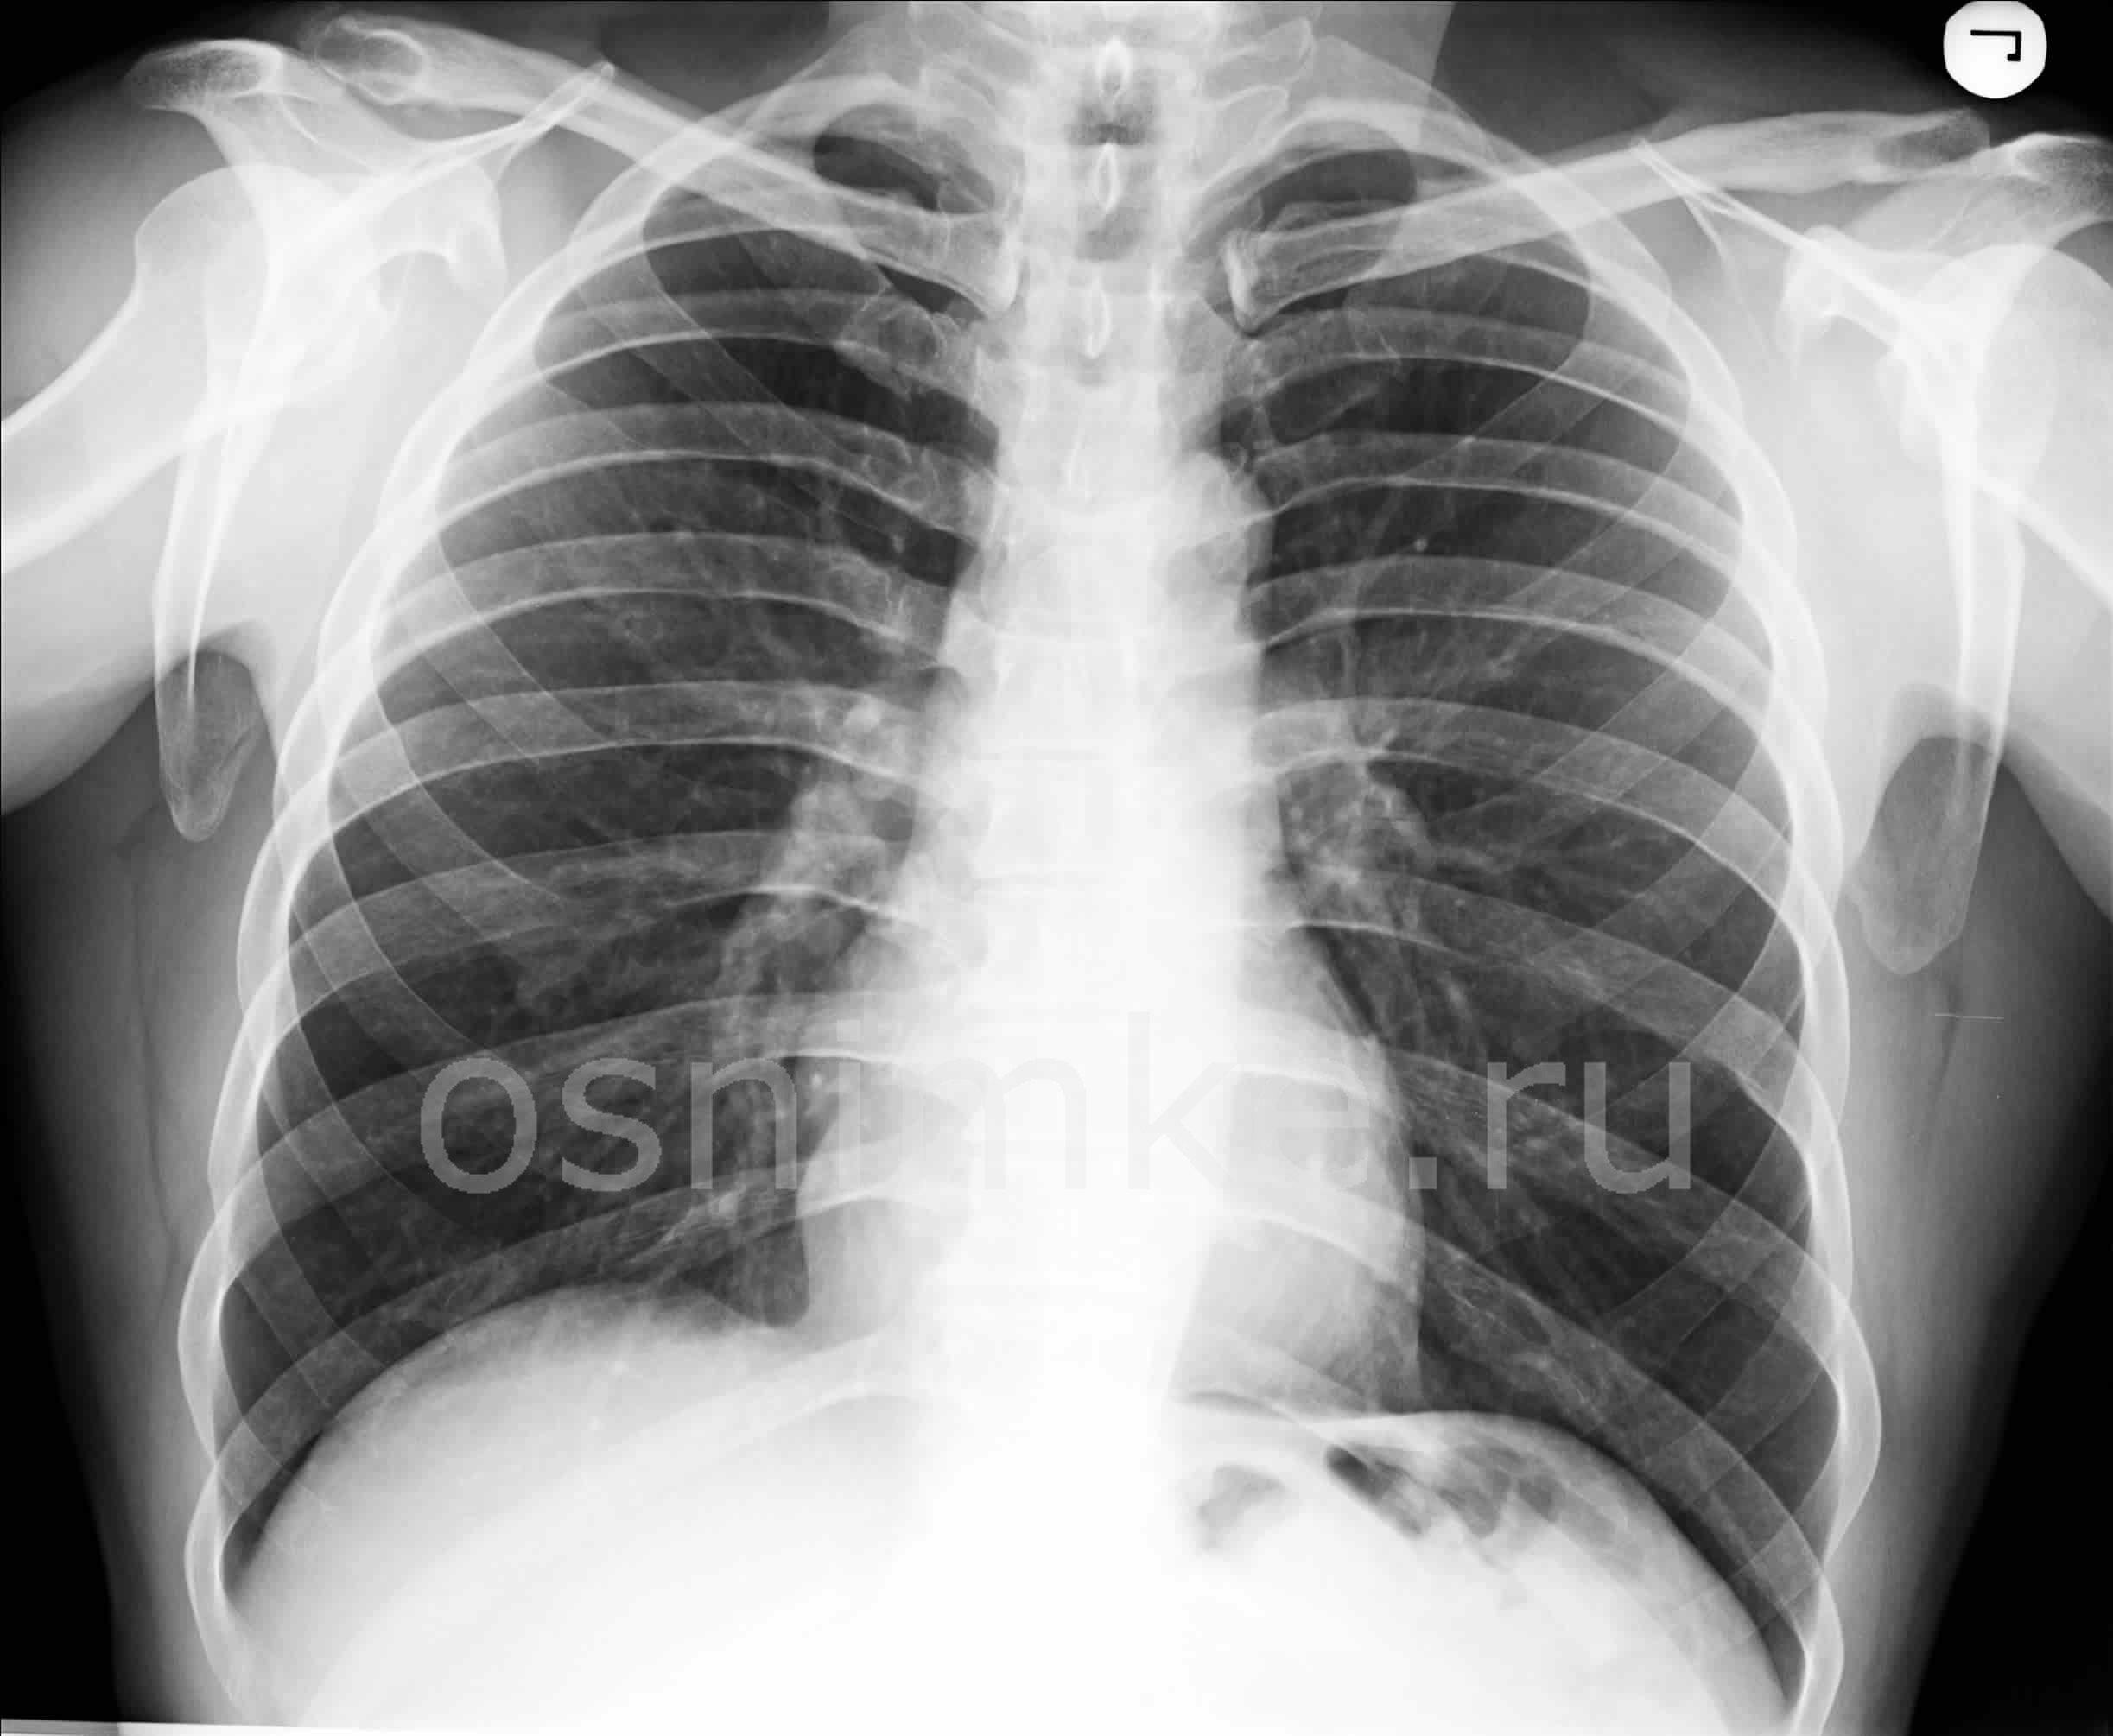

Как выглядит недуг на снимке

После проведения рентгенографии снимки должен изучить специалист, и на основе полученных данных и результатов других исследований сделать соответствующие выводы и поставить диагноз. В норме легкие и бронхи человека выглядят следующим образом:

- легочные доли имеют одинаковый, равномерный черный оттенок;

- в районе сердца наблюдается белый просвет;

- ребра и ключицы серые, с привычными очертаниями;

- купола диафрагмы белого цвета;

- позвоночный столб расположен в центре.

Признаки пневмонии на рентгеновском снимке во многом зависят от формы заболевания и его стадии, а также от локализации патологического процесса. Если исследование показало признаки пневмонии, необходимо как можно скорее приступить к лечению – запущенный патологический процесс опасен не только для здоровья, но и для жизни человека.

Основные признаки, описание

Первый признак пневмонии на рентгеновском снимке – появление очагов затемнения с неровными контурами в разных частях легкого, которые могут иметь разный размер, от 3-4-х до 12 мм.

Тени различают по внешнему виду (круглые, овальные кольцевидные) и интенсивности окраски – чем темнее пятно, тем сильнее выражен патологический процесс.

При поражении лимфатических узлов и нарушении кровоснабжения органа могут наблюдаться изменения корней легких, а если болезнь затронула плевру – нарушение в рисунке куполов диафрагмы. В остальном проявления пневмонии зависят от стадии, формы и клинических особенностей заболевания:

- Очаговая форма. На рентгене отображаются небольшие (1-1,5 см) тени со слабой или умеренной интенсивностью окраски, неоднородной структурой и нечеткими границами. Очаги поражения могут быть единичными или множественными, а в некоторых случаях они сливаются в одно большое пятно. Корни легких расширены, причем нарушения нормального рисунка органа могут сохраняться в течение нескольких дней после выздоровления.